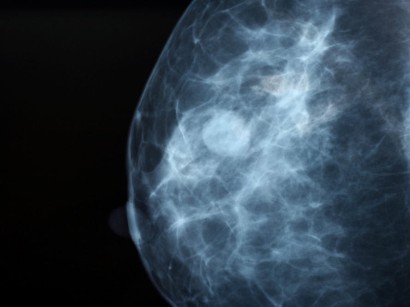

Jede Frau reagiert alarmiert wenn bei der Tastuntersuchung oder in der Mammografie etwas Verdächtiges gefunden wird ein Knoten in der Brust oder eine Gewebeveränderung die im Röntgenbild sichtbar wird. Die Indikation zur Abklä-rungsdiagnostik wird in der Konsensuskonferenz gestellt. Jahresbericht Evaluation 2018 Deutsches Mammographie-Screening-Programm Kooperationsgemeinschaft Mammographie.

Nun hat sich in vielen Mammographie-Screening-Programmen in Europa und den USA gezeigt dass die Tumorgröße durch Früherkennungsuntersuchungen positiv beeinflussbar ist und auch die Überlebensraten bei Brust-krebs durch die frühe Erkennung verbessert werden kann. Wenn in der Mammographie nichts zu sehen ist ganz gleich aus welchem Grund gilt der Befund als unauffällig das heißt. Diese Frauen bekommen von der Ärztin oder dem Arzt der Mammographie-Screening-Einheit einen eigenen Termin um das weitere Vorgehen zu besprechen.